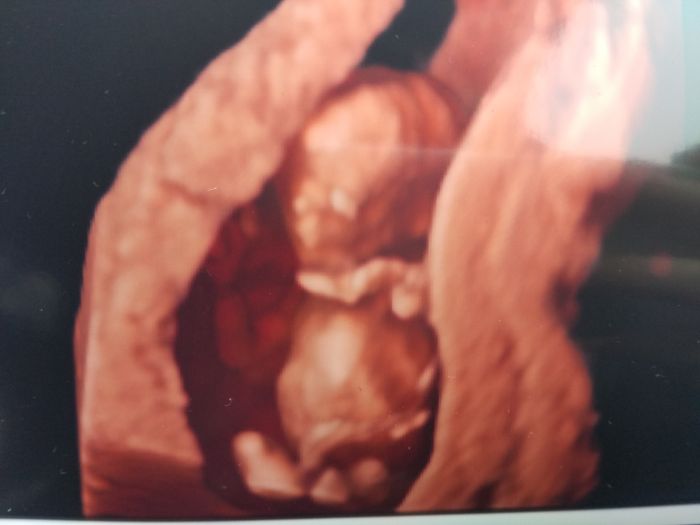

Holky,moc gratuluju!Emmy,to jsou krásné fotky!To se s těma smouhama,co jsme viděli my vůbec nedá srovnat..

S tim pohlavim je mi to jasny, ze jisty ke to az po porodu :D Mame doma hromady podedenych veci, takze blaznive nakupovat kvuli pohlavi zaplatpanbuh nebudeme :) Posilam vam nasi hopsalku....

Holky moje zlatý, ani nevíte, jak vam to přeji. Dokonce mi ukapla slzicka, když jsem viděla Vaše fotky. ;-) gratuluji